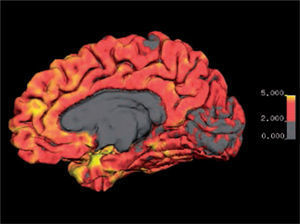

Imagen de espesor cortical de la cara medial del hemisferio derecho. Se visualiza espesor cortical mediante codificación por color entre los 0 y 5 mm. El espesor normal se encuentra entre los 2 y 5 mm., excepto en los lóbulos occipitales mediales en que el espesor puede ser menor a 2 mm.

Software Freesurfer (http://ftp.nmr.mgh.harvard.edu/).